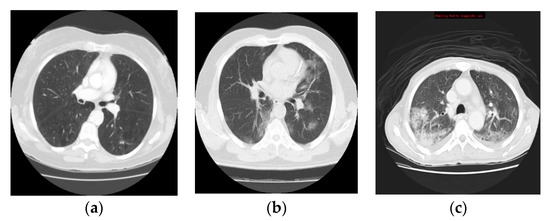

3.1. Data Collection